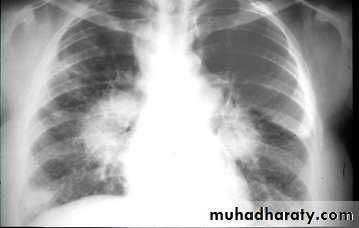

Bilateral enlargement of hilar nodes occurs in:

1- Sarcoidosis, which is far and away the commonest cause.The diagnosis is almost certain if the hilar enlargement is symmetrical and if the patient is asymptomatic, or has either erythema nodosum or iridocyclitis. Simultaneous enlargement of the right paratracheal nodes is common. Lung changes are sometimes visible.

2- Malignant lymphoma.

3- Tuberculosis. African and Asian races show this form of the disease in which substantial nodal enlargement can be a feature. It is rare to see bilateral hilar enlargement due to tuberculosis in Caucasians.

4- Fungal diseases, which are rare causes of bilateral hilar enlargement.

Identify main lower lobe pulmonary arteries: They can be compared to a little finger pointing downwards and medially. Sometimes, usually on the left side – it can appear only as the proximal phalanx of the finger.Interpretation: If the little finger shadow of the right lower lobe artery is not seen then you must check for evidence suggesting collapse of the right lower lobe.Identify the hilar point: Look for the site where the most superior upper lobe vessel – either vein or artery – crosses the lateral margin of the little finger. The point of crossing is known as hilar point and forms a horizontal “vee” (> or <).Interpretation: The left hilum must never be lower than the right hilum. Whenever a left hilum appears lower than the right hilum – look for other evidence suggestive of: 1- Collapse of either the left lower lobe or of the right upper lobe or 2- Enlargement of the right hilumBilateral hilar LNE